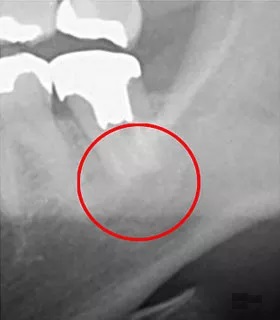

左の写真(スマホでは上写真)は一般的な歯科用の2次元のレントゲンので撮影した画像です。

赤丸で囲まれた部分も見た感じは特に問題なさそうに見えますが、3次元で撮影し回転させると歯の根っこの先に黒い影が出来ているのがわかると思います。

これは根尖病巣といって、バイ菌により骨が溶かされている部分です。

CT撮影することにより見えない部分を可視化して正しく診断しやすくなります。